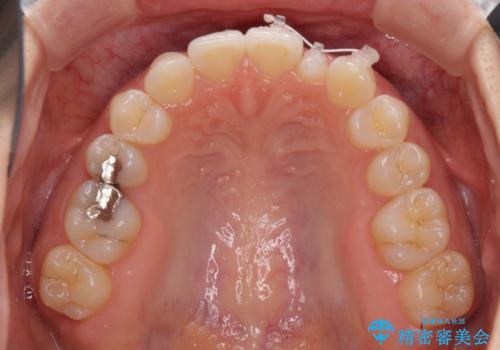

海外転居前に気になる前歯を整えたい 上下前歯の部分矯正

- 1年後に海外に転居するため、気になる前歯を矯正治療で整えたいとのことで来院された患者様です。

下顎は叢生が強かったため、奥歯までワイヤーを装着し、上顎は前歯の一部のみ気になっていたので、その部分にだけワイヤー装置を装着することとしました。